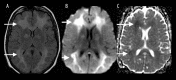

Toxic leukoencephalopathy results from damage to the white matter caused by various toxins. It manifests itself as white matter signal abnormalities with or without the presence of restricted diffusion. These changes are often reversible if the insulting agent is removed early, with the exception of posthypoxic leukoencephalopathy that can manifest itself 1-2 weeks after the initial insult. However, many other potential causes of white matter signal abnormalities can mimic the changes of toxic leukoencephalopathy. Thus, familiarity with the causes, clinical presentation and particularly imaging findings of toxic leukoencephalopathy is critical for early treatment and improved prognosis. The purpose of this pictorial essay is to familiarize the reader with the various causes of toxic leukoencephalopathy along with its differential diagnoses and mimics.